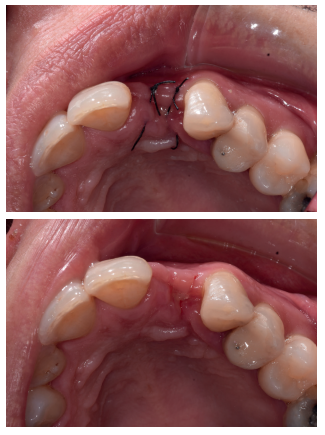

Se colocó el injerto entre la superficie vestibular del implante, y la cortical vestibular, para cubrir el injerto con una esponja de fibrina (Gelatamp®) y dar dos puntos simples de sutura con poliamida no absorbible de 4/0 (Supramid®), realizando una radiografía periapical en el post-operatorio inmediato, para verificar la colocación adecuada del implante y del material de injerto (Figura 7). Así mismo, y con el objetivo de valorar el mantenimiento de la cortical vestibular se realizó un escáner de haz cónico realizado en el post-operatorio inmediato (Figura 8).

herida (B), radiografía periapical en el post-operatorio inmediato (C).

de dentina rellenando el gap.

Transcurrida una semana, se procedió a la retirada de la sutura, observando una buena cicatrización de los tejidos blandos (Figura 9).